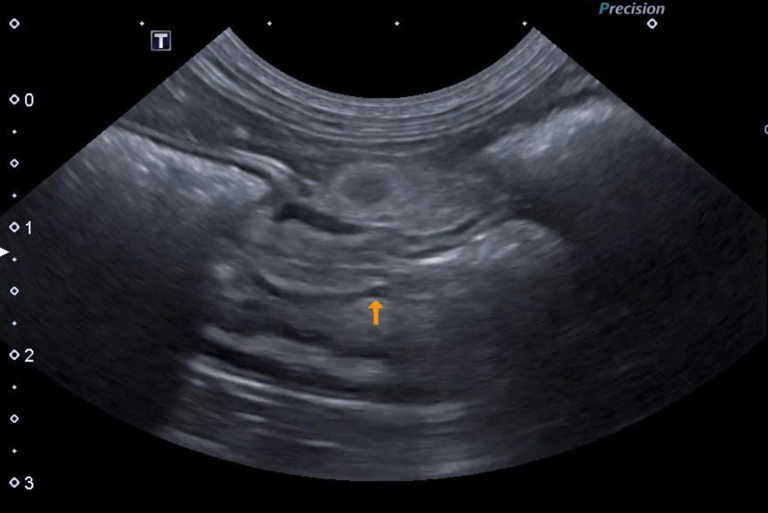

4 - Est ce que l’image obtenue vous semble correcte ?

A - Oui

B - Non

C - Je ne sais pas

5- Si non, expliquez quel réglage serait intéressant de modifier pour obtenir une image échographique correcte

A - J'ai coché oui à la réponse précédente

B - Diminuer la profondeur

C - Augmenter la profondeur

D - Augmenter le gain étagé en profondeur

E - Diminuer le gain étagé en profondeur

6- De quel organe s’agit-il ? Précisez G ou D et le plan de coupe réalisé

A - Le Rein Gauche en coupe transversale

B - Le Rein Droit en coupe transversale

C - Le Rein Gauche en coupe longitudinale

D - Le Rein Droit en coupe longitudinale

E - La Surrénale droite en coupe transversale

Question 4 : Réponse B

Question 5 : Réponse B

Question 6 : Réponse C

Question 7 : Réponse A